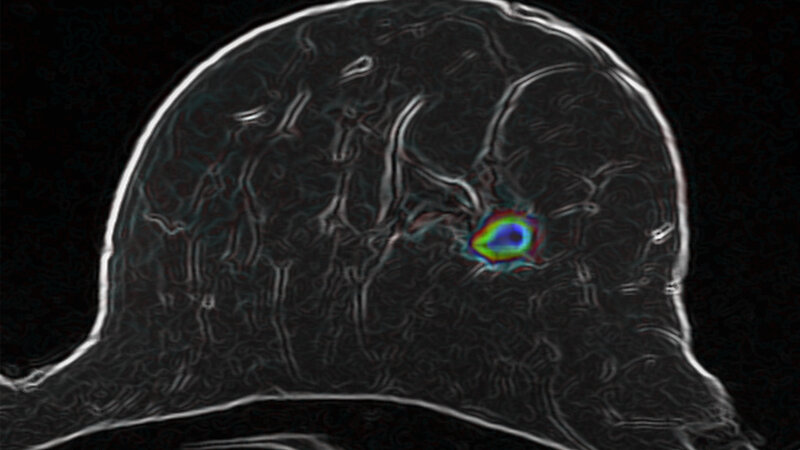

Der Radiologe hat sich daher gemeinsam mit seinen Kollegen daran gemacht, die diffusionsgewichtete Magnetresonanz-Tomographie (MRT) für die Untersuchung der weiblichen Brust zu optimieren und mit intelligenten computerbasierten Bildanalyseverfahren zu verbinden. Mit der diffusionsgewichteten MRT lässt sich die Bewegung der Wassermoleküle im Gewebe sichtbar machen und mit Hilfe eines Computeralgorithmus beobachten. Bösartige Tumoren verändern die Gewebestruktur, was sich auf die Bewegungsmuster der Wassermoleküle auswirkt.

Jetzt belegen die DKFZ-Wissenschaftler in einer von der Dietmar-Hopp-Stiftung geförderten Studie, dass die optimierte diffusionsgewichtete MRT in Kombination mit intelligenten Bildanalyseverfahren tatsächlich zuverlässige Aussagen über bösartige Veränderungen in der Brust erlaubt. Dazu untersuchten sie insgesamt 222 Frauen, die sich nach einem auffälligen Mammographiebefund einer Biopsie unterziehen sollten. Bevor die Gewebeprobe genommen wurde, analysierten die Forscher das Brustgewebe der Studienteilnehmerinnen mit ihrer neu entwickelten Methode.

Das vielversprechende Ergebnis: Die Zahl der falsch positiven Befunde ließ sich in der Studiengruppe um 70 Prozent reduzieren. Tatsächlich vorhandene bösartige Veränderungen konnten die Wissenschaftler in 60 von 61 Fällen erkennen. Das entspricht einer Trefferquote von 98 Prozent und ist vergleichbar mit der Zuverlässigkeit von MRT-Methoden, bei denen Kontrastmittel zum Einsatz kommen.

„Wir werten die Aufnahmen mit Hilfe einer von uns entwickelten, intelligenten Software aus“, erklärt der Informatiker Paul Jäger, der sich mit Bickelhaupt die Erstautorschaft der Studie teilt. „Das macht die Methode weitgehend unabhängig von der Interpretation durch einzelne Ärzte.“ Auf diese Weise lässt sich gewährleisten, dass die Methode an verschiedenen Studienzentren gleichermaßen zuverlässige Ergebnisse erzielt.